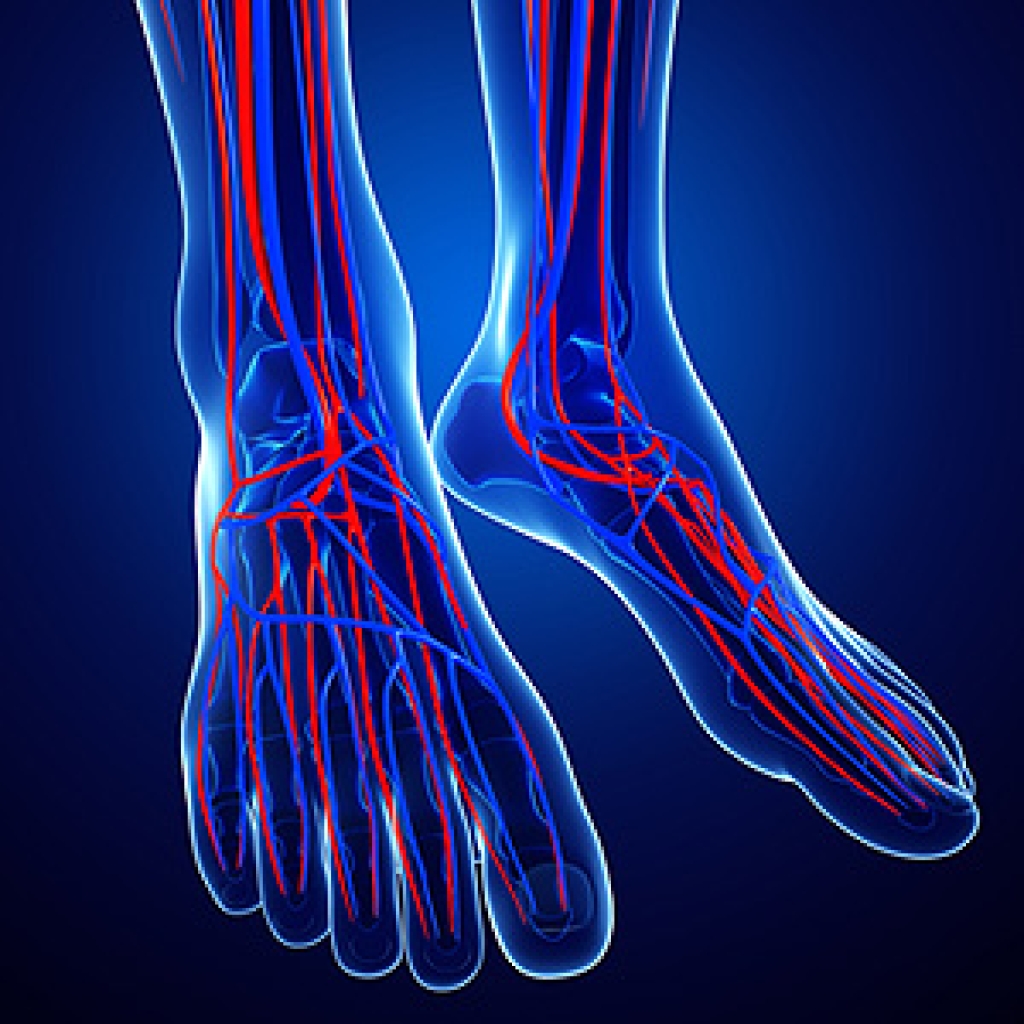

Circulation describes the movement of blood throughout the body. Having good circulation in your legs and feet is essential for good health, but sometimes our circulation can deteriorate as we age or can become worse due to certain medical conditions. Fortunately, there are things that you can do to improve circulation throughout your body. Doing light exercises, such as walking and stretching, increases blood flow throughout the body and can lower your blood pressure. Sitting in a position that does not cut off circulation to your legs is also very important. Try sitting in a chair with your legs spaced slightly apart and your feet on the floor rather than sitting cross legged. If you are a smoker, quitting can improve both your overall health and your circulation. If you have poor circulation in your lower limbs, it is recommended that you consult a podiatrist for treatment.

Poor blood circulation in the feet and legs is can be caused by peripheral artery disease (PAD), which is the result of a buildup of plaque in the arteries.

Plaque buildup or atherosclerosis results from excess calcium and cholesterol in the bloodstream. This can restrict the amount of blood which can flow through the arteries. Poor blood circulation in the feet and legs are sometimes caused by inflammation in the blood vessels, known as vasculitis.